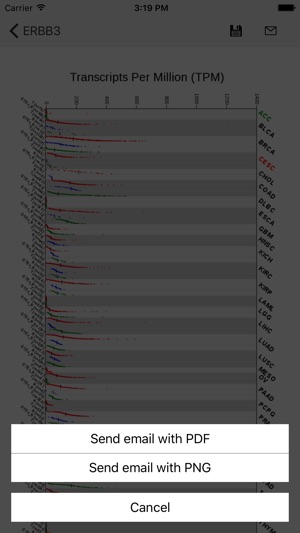

This GE-mini APP is designed to exhibit gene expression profiling of a given gene over many tissue types including tumors. The underlying data are based on RNA Sequencing results from both TCGA and GTEx after they are normalized and integrated. The current version, based on the September 2015 release of TCGA and the phs000424.v6.p1 release of GTEx, contains >19,000 total samples across 33 cancer types and 53 normal tissue types.